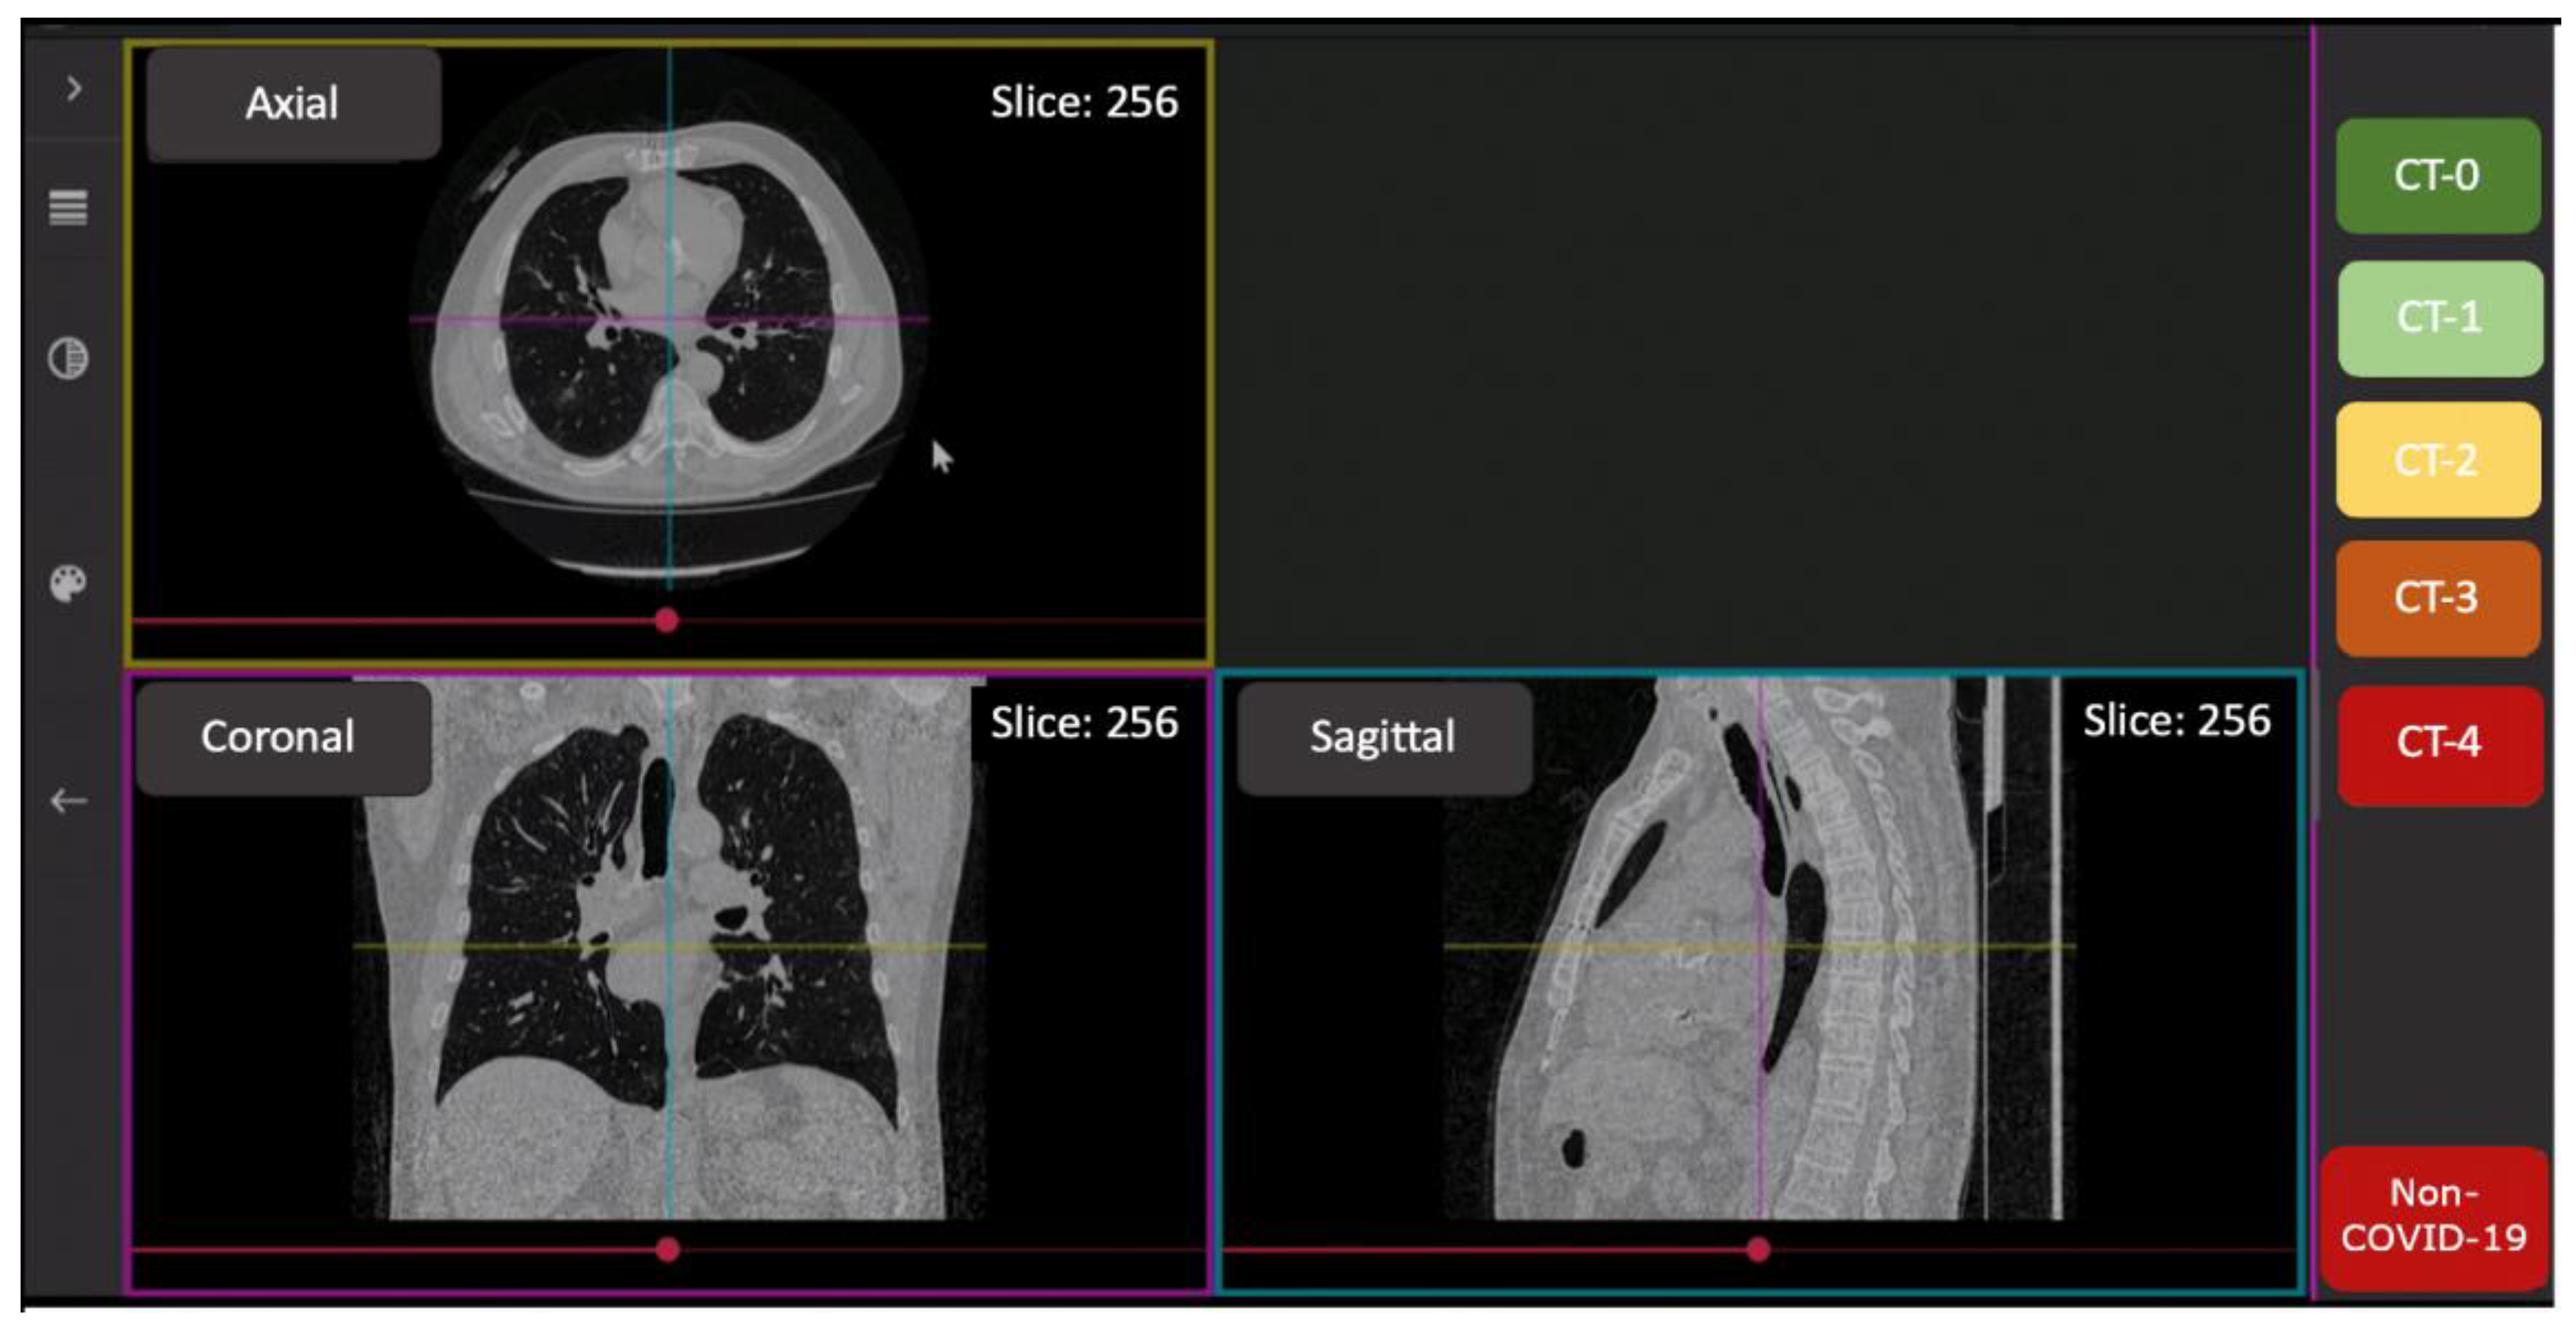

3.3. Image Analysis